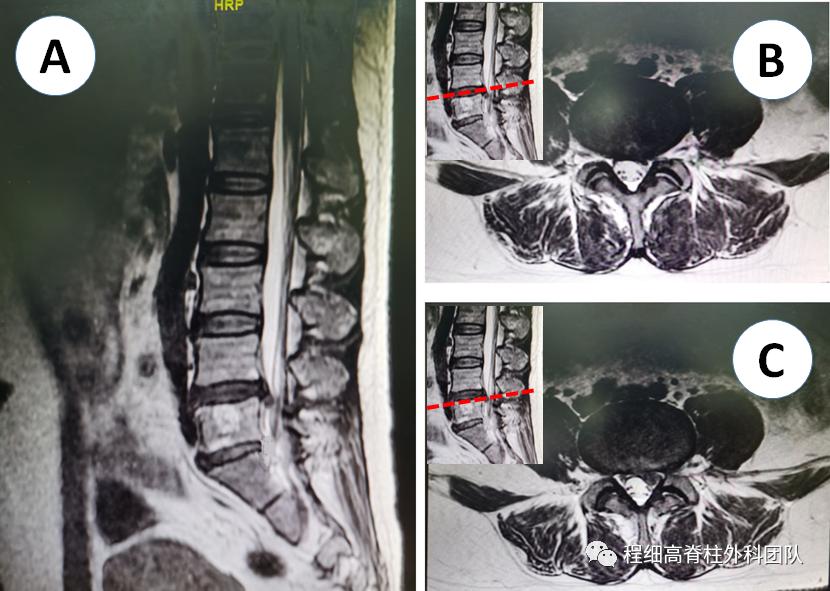

48岁女性,杨某,因“左下肢麻痛1月”入院。既往因右侧腰腿痛行L5/S1椎间孔下椎间盘入路髓核摘除术,术后至今右下肢症状完全缓解。异常查体:左大腿后侧、小腿外侧及足底浅感觉减退,左下肢直腿抬高试验阳性(30°)。在南昌大学第二附属医院腰椎磁共振示L4/5椎间盘左后脱垂。程细高教授带领微创脊柱外科团队为患者制定了微创内镜下椎板间入路L4/5髓核摘除术,术中精准放置通道,取出大块脱垂髓核,术后麻痛症状明显缓解,直腿抬高试验转为阴性。

图1 术前磁共振示L4/5椎间盘左后脱垂